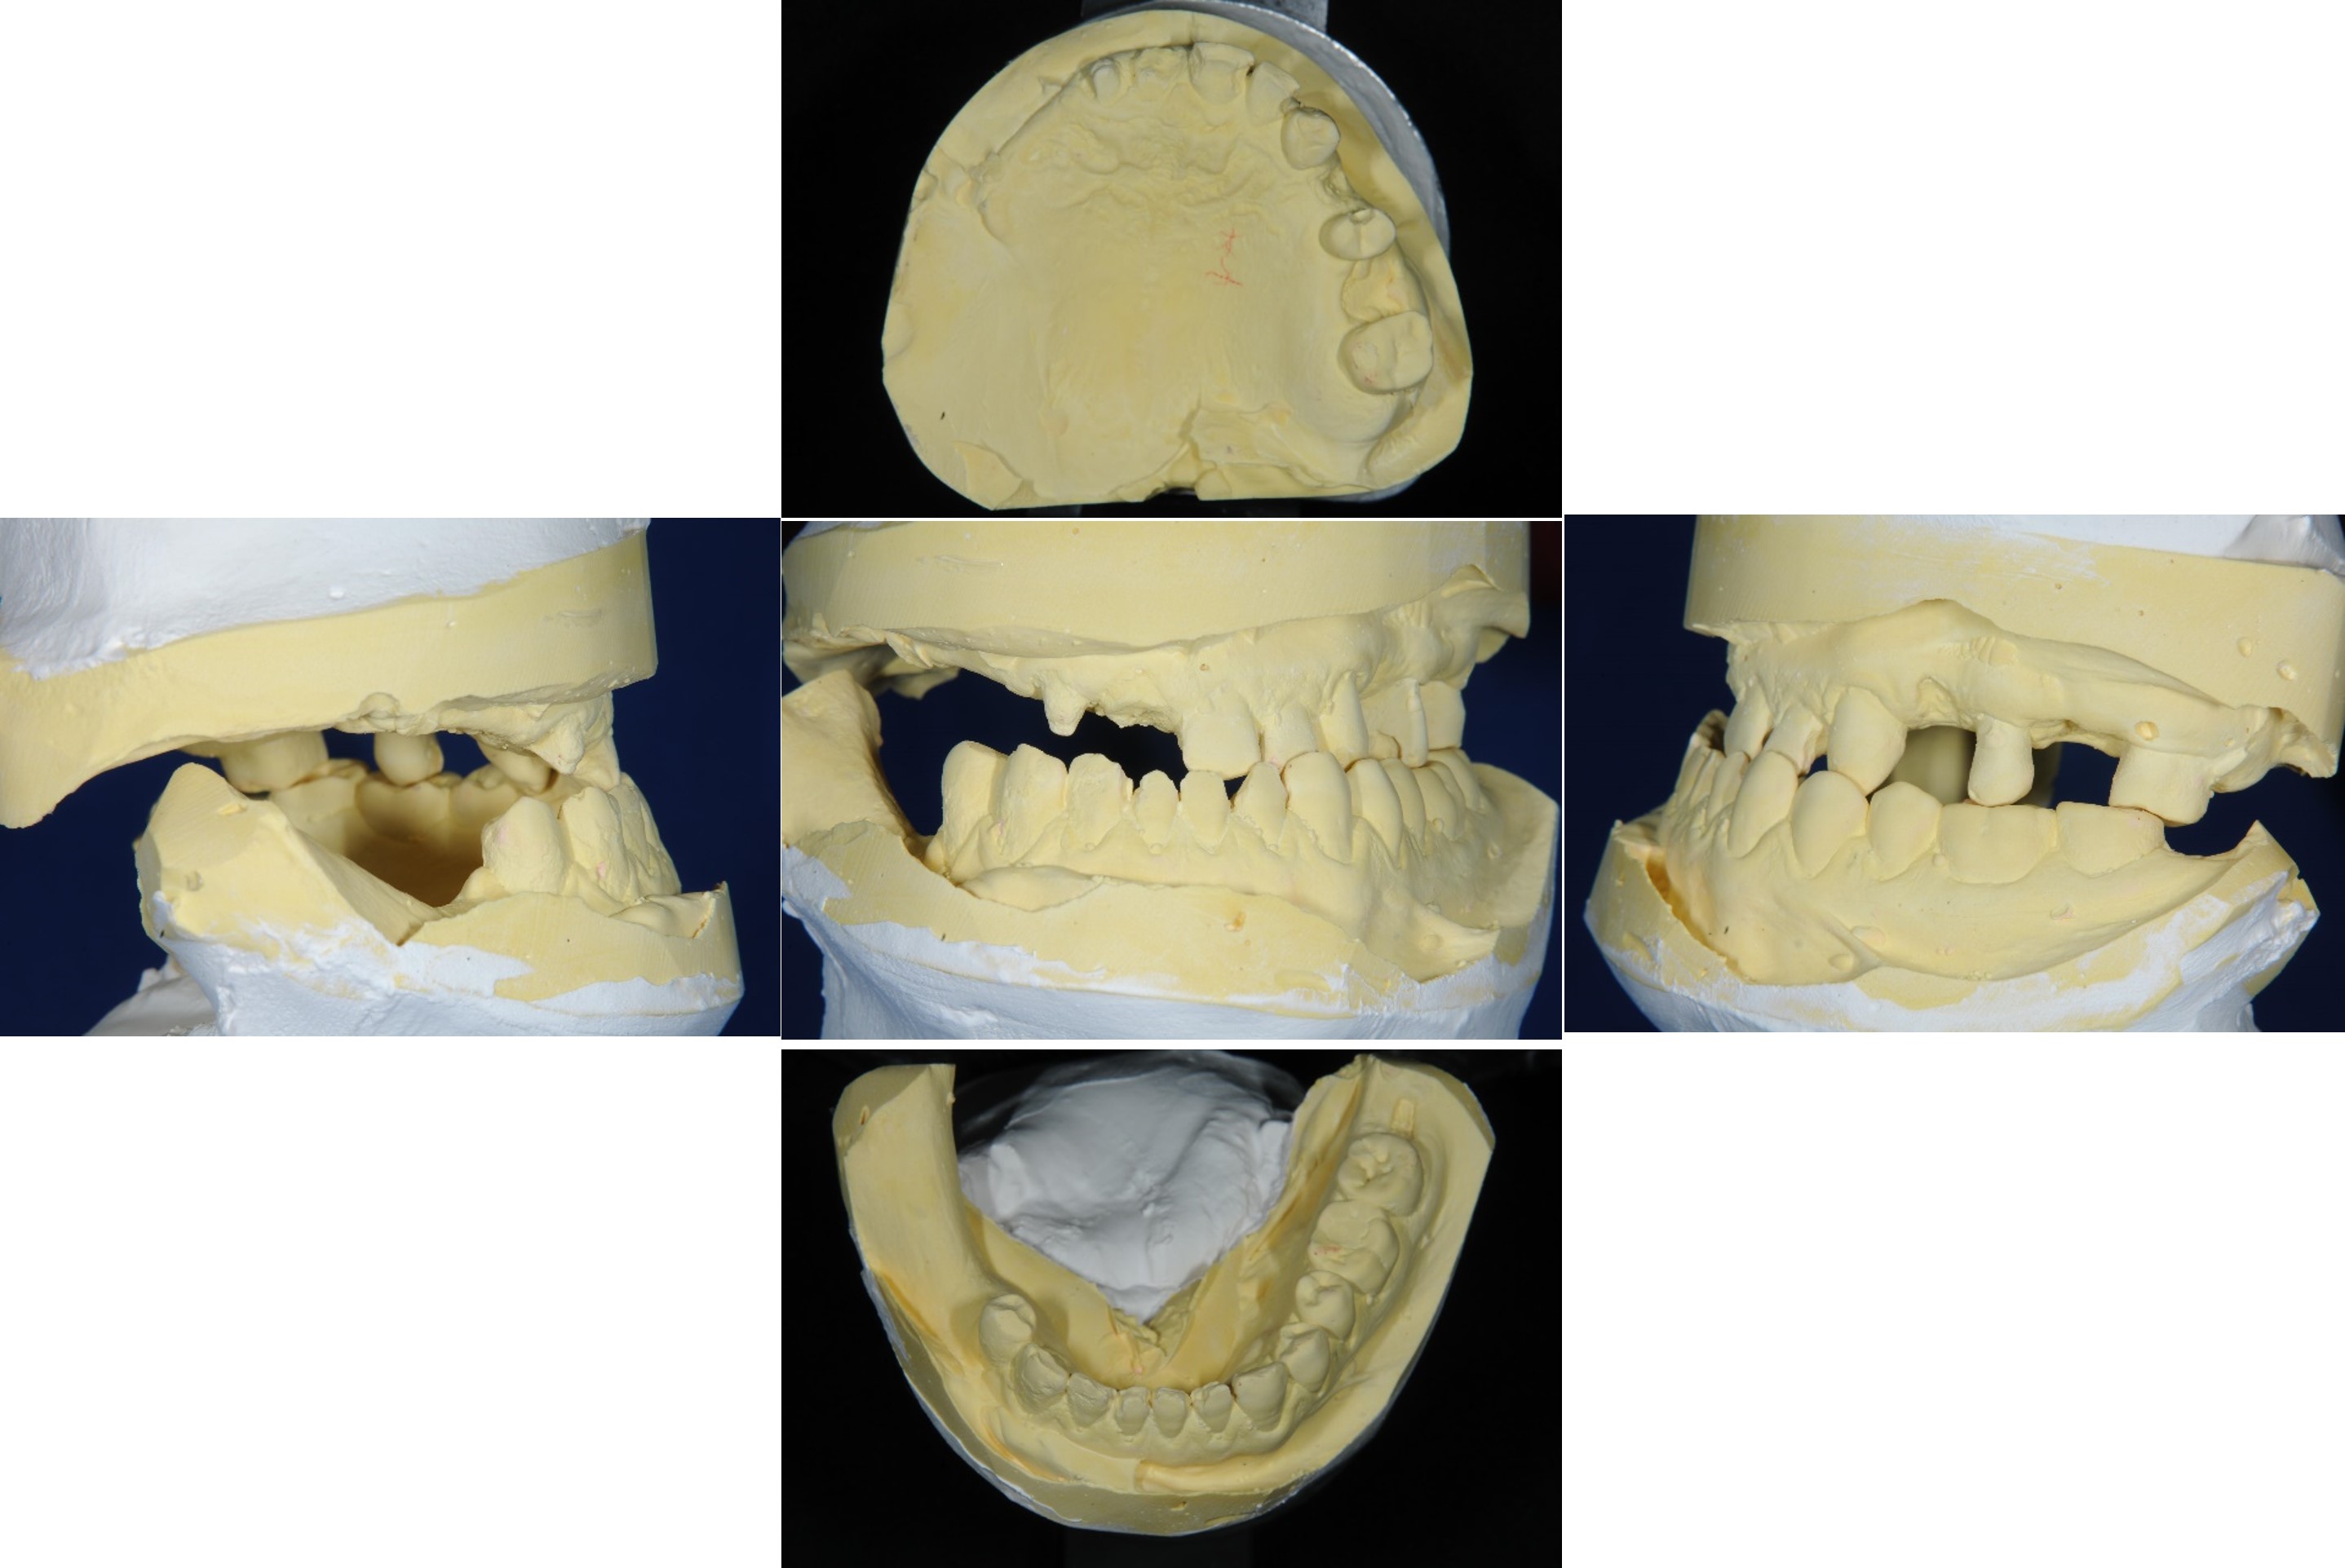

模型咬合分析

蠟型模擬最終可能成果